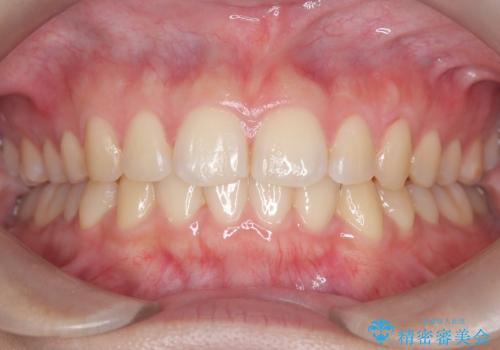

驚くほど短期間で前歯のガタツキを解消! マウスピース矯正の効果

奥歯の噛み合わせは綺麗に噛んでいたため、前歯の叢生(でこぼこ)を、短期間で治療完了するように計画しました。

奥歯の噛み合わせは整っていたため、前歯の並びを美しく修正することに専念できました。マウスピース矯正による治療で短期間で改善しました。